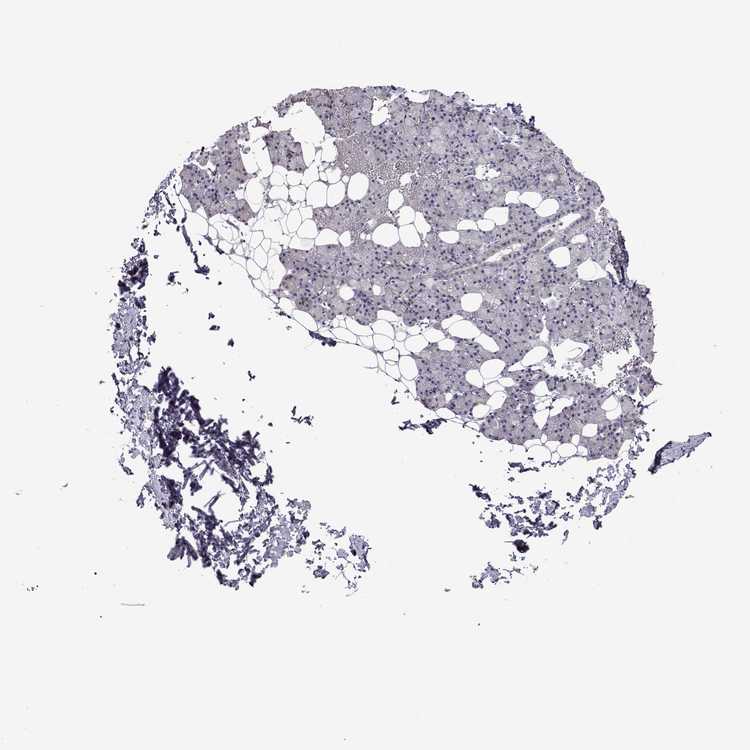

Antibody HPA072287

Glandular cells Not detected